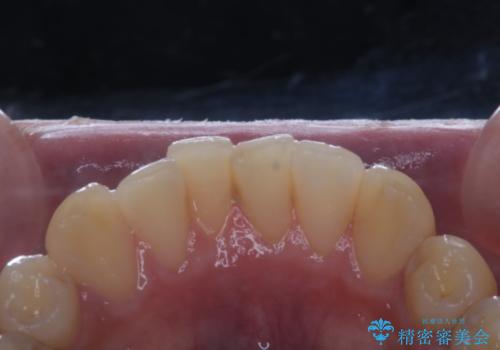

日々の磨き残しや唾液の成分などによりバイオフィルムや歯石はどうしても付着してしまいます。歯石や汚れを放置していると、そこで病原菌が繁殖す始めます。歯肉に炎症が生じると歯周病などの引き金となります。

そのため、2~3か月に1回は、歯科医院での専門的クリーニングをすることが大切です。